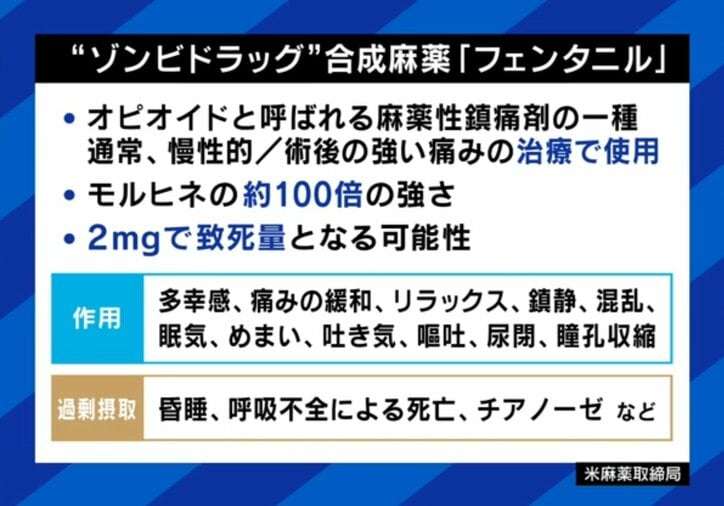

2mgで致死量「フェンタニル」中毒者だらけの“ゾンビタウン”とは?在米日本人「処方された薬に入ってる」「警察は見て見ぬフリ」